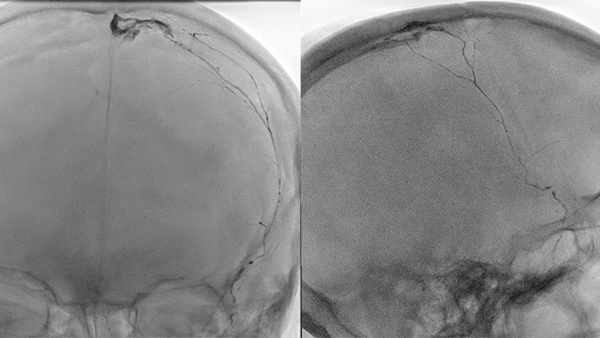

Incidental cerebral venous thrombosis during Middle Meningeal Artery embolization with Squid for chronic subdural hematoma